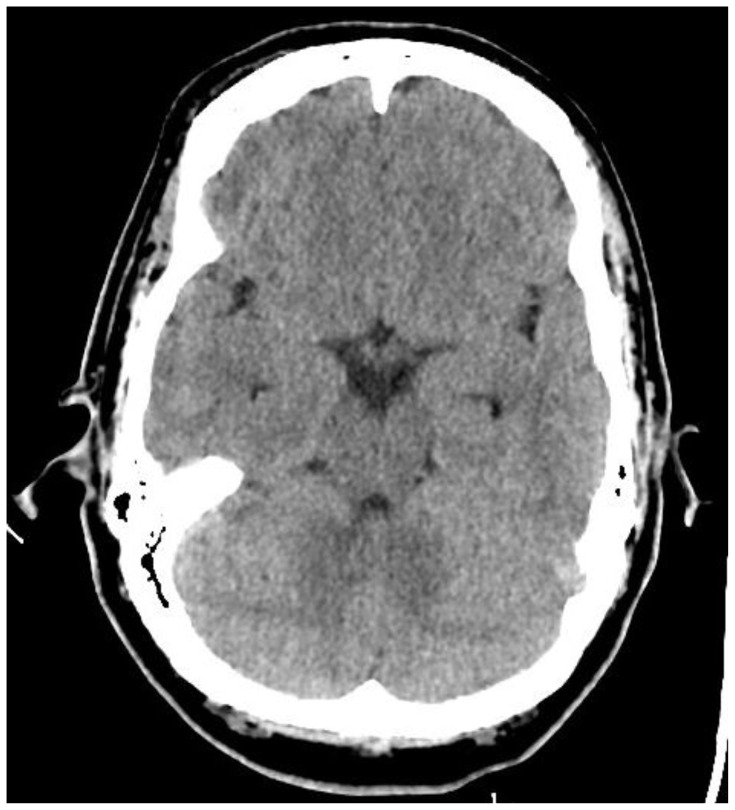

Introduction: Headache is the fifth most common chief complaint in the emergency room, and the vast majority are ultimately diagnosed as benign primary headaches.1,2 However, subarachnoid hemorrhage (SAH) is one of several critical diagnoses which can present as a headache. With a case fatality rate of up to 66.7% in some instances, SAH is considered a "can't miss" diagnosis.3Subarachnoid hemorrhage is classically associated with a thunderclap headache, one definition of which is a headache that reaches maximal intensity within one minute or less and reaches a seven out of ten in severity.1 Unfortunately, a thunderclap headache is not as sensitive nor specific for SAH as is often taught. In one study, only 50% of patients with an aneurysmal subarachnoid hemorrhage presented with a thunderclap headache and an additional 19% of SAH headache came on more gradually over the course of five minutes.4 A second study found that only 66% of SAH patients reported a thunderclap headache.2 Thunderclap headaches can also be associated with other intercranial pathology including intracerebral hemorrhage, cerebral venous thrombosis, cervical artery dissection, posterior reversible encephalopathy syndrome, meningitis, and temporal arteritis among others.1,2 In a large observational study, SAH accounted for 32% of the serious pathology cases identified in patients with a thunderclap headache. Even among the thunderclap headache cohort, however, 88% of patients ultimately had a benign diagnosis (compared to 93% of patients who did not report a thunderclap headache).2Additional signs and symptoms of SAH include seizures in 6-9% of patients, vomiting, neck pain and stiffness, visual disturbances, loss of consciousness, and focal cranial nerve or supratentorial deficits.1,5 A non-contrasted computer tomography (CT) of the head within six hours of headache onset can have a sensitivity of 98.7 to 100%; however, the sensitivity decreased to 86% at the 24-48 hour mark.1,6 A meta-analysis found a pooled six hour sensitivity of 1.0 and asserts that a head CT interpreted as negative by an attending radiologist effectively rules out SAH in neurologically intact patients with a defined onset of a thunderclap headache.6 Some guidelines in the United States still recommend shared decision making with the patient to choose between a Lumbar Puncture (LP), Computer Tomography Angiogram (CTA), or no further testing to rule out SAH in the case of a negative head CT.2 The more time that has elapsed between onset and CT imaging, the stronger the recommendation to pursue further testing. A negative head CT followed by a negative LP approaches 100% sensitivity for ruling out SAH, and a negative head CT with a negative CTA has a 99.4% probability of ruling out SAH.1,3 Thus it is an important learning point that if a headache has been ongoing for more than six hours and there is a high pre-test probability for an SAH, a negative head CT is not sufficient to rule out the diagnosis, and a secondary test should be ordered.Status epilepticus is defined as five minutes of continuous seizure activity or repeated seizures without return to baseline between seizures.7 The immediate priorities for a seizing patient include providing supplemental oxygen, considering intubation if patient is unable to protect airway, obtaining IV access if not previously established, and checking glucose.7 The main priority for a patient in status epilepticus is to stop the seizure with seizure abortive medications, typically benzodiazepines, and treat life-threatening causes of status epilepticus.7 This simulation will enable learners to diagnose SAH that is not the classical "worst headache of my life" and manage an actively seizing patient.

Educational objectives: At the conclusion of the simulation leaners will be able to:Efficiently take a history from the patient and perform a physical exam (including a complete neurological exam)Identify red flag symptoms in a patient complaining of a headacheOrder and interpret the results of a CT of the head and either a CT angiogram of the brain or a lumbar puncture to make the diagnosis of subarachnoid hemorrhageDemonstrate appropriate management of a seizureCheck a fingerstick glucoseProvide supplemental oxygenAdminister an IV or IM benzodiazepine to treat the seizureUtilize the I-PASS framework to communicate with the inpatient team during the transition of care.